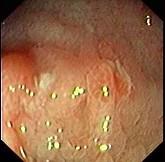

问题 女,26岁,反复右下腹疼痛4年,伴糊状腹泻,无粘液和脓血。查体:右下腹压痛,未触及包块。结肠镜检查如图,多部位活检发现炎症细胞浸润,以淋巴细胞为主,有非干酪样肉芽肿。最可能的诊断为 ( )

选项 A.溃疡性结肠炎 B.Crohn病 C.肠结核 D.慢性阑尾炎 E.细菌性痢疾

答案 B